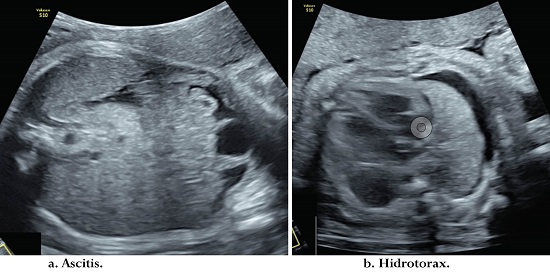

Mujer de 18 años que ingresó a la institución el 18 de octubre de 2019, estado civil soltera, oriunda de Venezuela y residente en Bogotá desde hace 3 meses. Consultó al servicio de urgencias por dolor pélvico con gestación de 29 semanas. Ninguna otra sintomatología. Antecedentes médicos negativos. Antecedentes gineco-obstétricos: 3 gestaciones, 2 partos, sin abortos, 2 hijos vivos. No había iniciado control prenatal hasta ese momento. Examen físico: deprimida con llanto fácil, signos vitales: frecuencia cardiaca 90 lpm, presión arterial 108/70 mmHg. Altura uterina de 28 cm y fetocardia 144 lpm. Hallazgos positivos: altura uterina de 29 cm fetocardia 150 lpm. Se tomaron paraclínicos: hemograma: leucocitos 8 450 x mcl Hb: 12,5 gr/dl, creatinina: 0,4 mg/dl, hepatitis B: negativa, prueba VIH: negativa, prueba treponémica rápida: positiva y VDRL positiva en 1: 32 diluciones. Se realizó el diagnóstico de caso probable de sífilis gestacional. Ultrasonido obstétrico: biometría para 30,1 semanas. Crecimiento fetal normal. Líquido amniótico normal. Hallazgos positivos: hídrops fetal con presencia de ascitis, hidrotórax; además, presencia de hepatomegalia. El doppler de arteria cerebral media sin evidencia de anemia fetal (Figura 4). Se decide hospitalizar, esquema de maduración pulmonar fetal, neuroprotección fetal con sulfato de magnesio y tratamiento con penicilina endovenosa de 5 millones de unidades cada 4 horas por 14 días por considerar sífilis gestacional con afectación fetal severa. Se da tratamiento a la pareja con penicilina benzatínica por 3 dosis. Evolución: Se realizó control con ultrasonido a las 24 horas. Doppler de arteria cerebral media: anemia severa. Se realiza control ecográfico a las 48 horas. Doppler de arteria cerebral media: anemia leve y persistencia de hídrops fetal. Paciente con evolución clínica satisfactoria. Control ecográfico a los 7 días. Doppler de anemia cerebral media normal. Líquido amniótico normal. Sin signos de hídrops fetal. Se dio egreso de la institución.

Inició trabajo de parto espontáneo a las 36 semanas y 2 días. Prueba treponémica rápida: positiva. VDRL negativa, obteniendo recién nacido cuyo peso fue de 2,460 gr, talla 48 cm, perímetro cefálico 32 cm, puntaje APGAR 8-9-9. Se toma control de VDRL a la madre en el ingreso a sala de partos reportado como 1:16 diluciones. El nacimiento sucede sin complicaciones, el examen físico del recién nacido es normal y el VDRL a las 12 horas es de 1:8, se toman paraclínicos para descartar sífilis congénita que son negativos (hemograma, radiografía de huesos largos, líquido cefalorraquídeo, uroanálisis y función hepática). La paciente y el recién nacido permanecen en alojamiento conjunto 24 horas posterior al parto. Se administra penicilina cristalina al recién nacido de manera profiláctica 50.000 UI/Kg/IM dosis, y se realiza seguimiento a la semana; no se evidencian complicaciones maternas o del recién nacido.